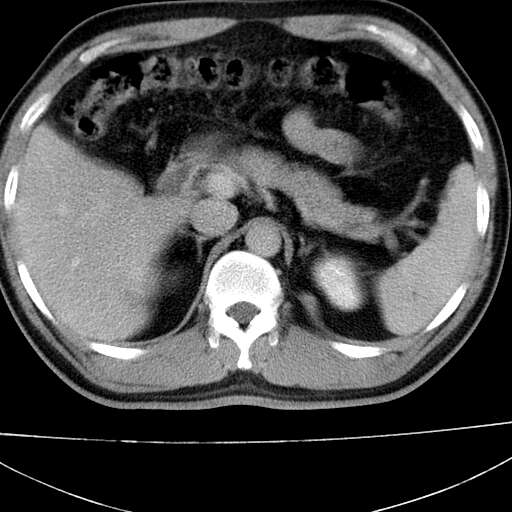

标题: CT21921:腹膜后腔肿物。患者男39Y。体检。增强扫描时间欠准

左侧膈肌脚外缘见一结节样软组织影,密度较均匀,与胸膜关系稍密切,增强轻度强化;考虑来自胸膜良性病变(胸膜纤维瘤可能)。建议加扫胸部ct检查。

2、左下膈肌脚外缘结节状病变,与胸膜交界面呈锐角,胸膜下脂肪线可见,定位于肺内,考虑支气管囊肿或肺隔离征可能性大。

1)考虑左肺下叶后基底段(或左下胸后壁胸膜)软组织团块,性质待定;建议行进一步检查。2)左肾结石。

左膈肌连续性中断,左侧膈疝可能性大.

左膈肌角后腹膜腔见肿物影,其内见脂肪密度灶及软组织密度灶,强化不明显。病灶大部在后腹膜内。考虑异位嗜铬细胞瘤或脂肪肉瘤、畸胎瘤

1)考虑左肺下叶后基底段软组织团块,性质待定;建议行进一步检查。2)左肾结石。

左膈肌连续性中断,左侧膈疝可能性大

左下肺隔离症,可见从胸主动脉发出异常血管供应